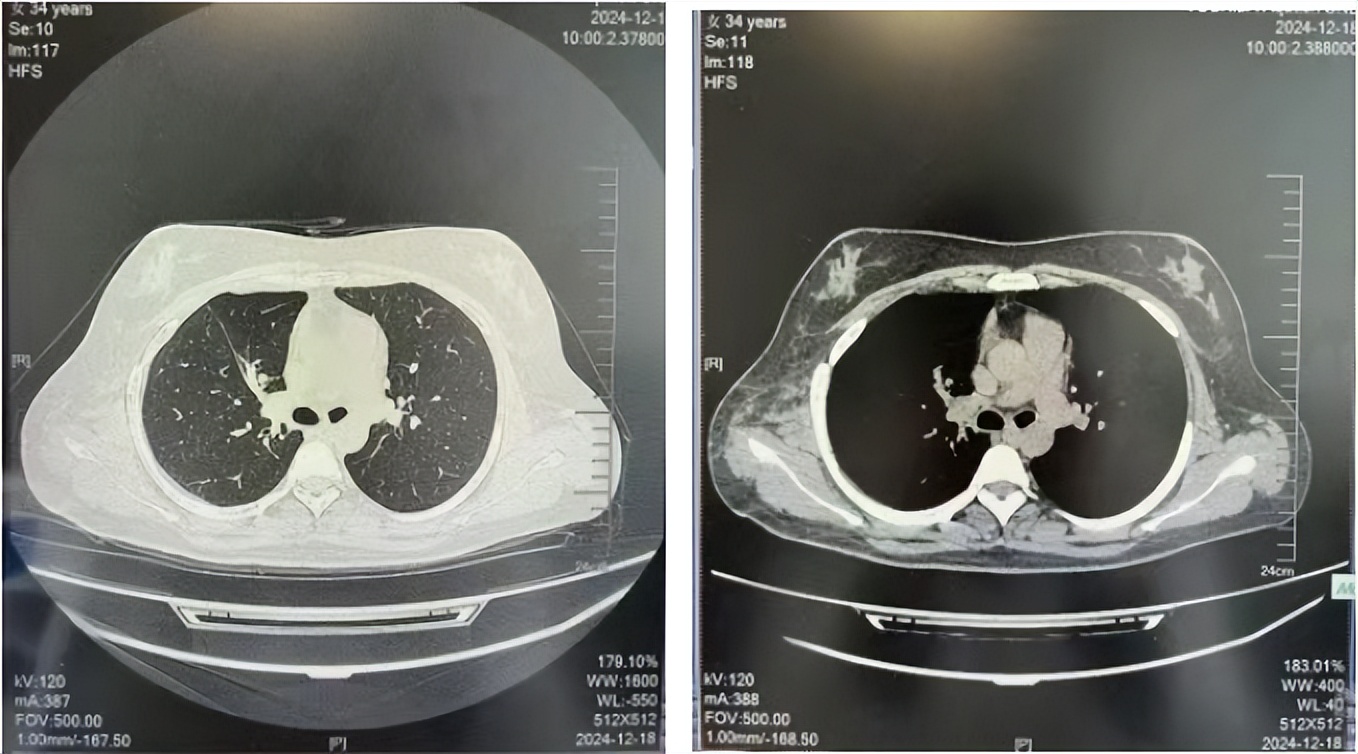

2024.12

34岁,女性,无吸烟史饮酒史,既往体健。2015年11月无明显诱因出现咳嗽咳痰,痰为黄色粘液状,就诊于铁西华康医院,胸部CT示右肺上叶尖段可见结节影,邻近胸膜局限牵拉。2015年12月于胸科医院行肺肿物穿刺活检病理回报为肺腺癌。2015年12月16日全麻下行右肺上叶肺癌根治术及纵隔淋巴结清扫术,术后病理:肺组织中部分脉管内见腺癌组织,断端支气管旁淋巴结内见癌组织,淋巴结中见到转移癌(2/6),未行基因检测。

2016年1月复查CT提示支气管截断可见新发小结节,一线治疗采用培美曲塞+DDP方案化疗4周期(培美曲塞3.36,DDP 480mg)。化疗后复查胸部CT:右肺见不规则结节样影,最大层面大小约19mm*8mm,较前比较明显增大,疗效评估PD。2017.3-2017.4予单药多西他赛化疗3周期,疗效评估SD。2018年5月末复查CT提示结节较前增大,评效为PD,2018年6-10月予多西他赛+CBP化疗4周期,疗效评估SD。2022年5月患者出现活动后气短,复查胸部CT示右肺膨胀不良;右侧胸腔积液增多。胸腔积液包埋病理示符合肺腺癌细胞。行NGS基因检测:EML4:exon13-ALK:exon20融合。PD-L1(克隆号22C3)TPS<1%。

临床诊断:右肺上叶恶性肿瘤rT0N0M1a IVA期(第9版分期);恶性胸腔积液。

诊疗经过:2022年5月始口服克唑替尼3个月,出现肝功能异常(DILI 2级伴临床症状),改用恩沙替尼靶向治疗至今,目前评效为维持PR。恩沙替尼应用期间出现轻度肝功能异常(DILI 1级),对症处理后好转。截止目前PFS 33个月。